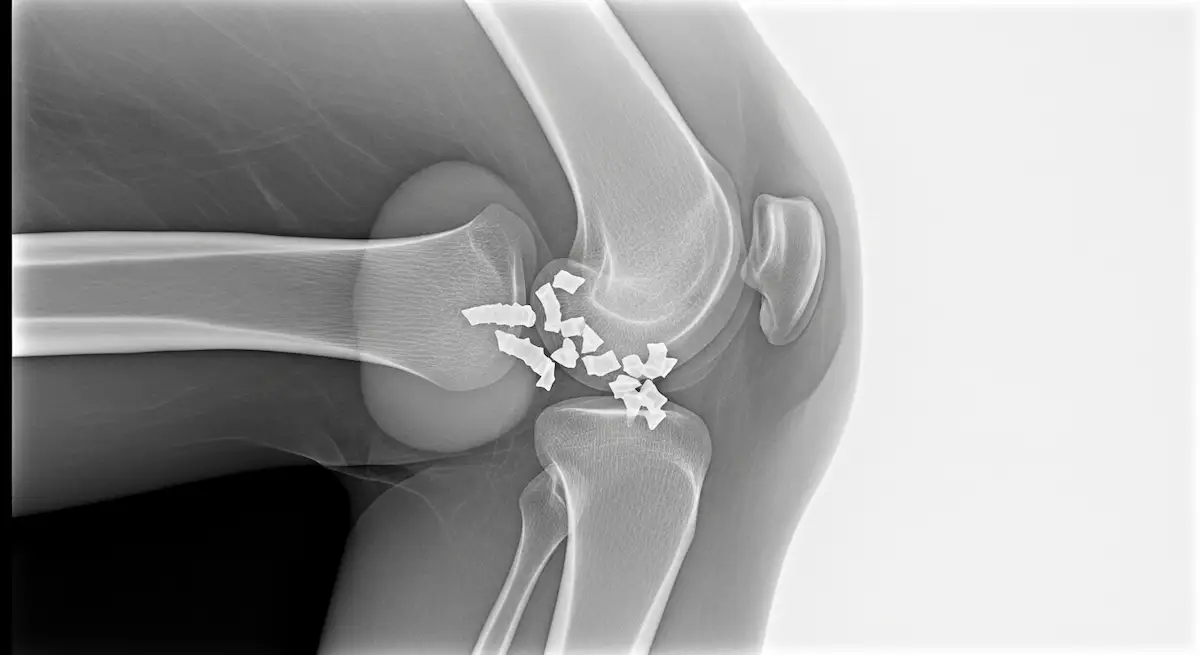

Peço radiografia quando o quadro foge do padrão, para verificar fragmentos na tuberosidade tibial ou excluir outras causas, e a ressonância fica para dúvidas pontuais.

A indicação cirúrgica é rara e reservada a casos persistentes após a maturidade esquelética, com fragmentos ósseos dolorosos não responsivos ao tratamento conservador.